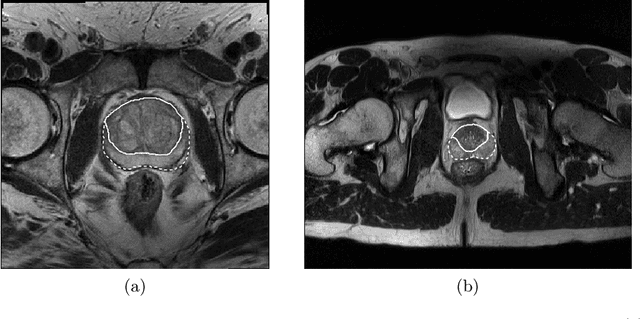

Abstract:Prostate cancer is the most common malignant tumors in men but prostate Magnetic Resonance Imaging (MRI) analysis remains challenging. Besides whole prostate gland segmentation, the capability to differentiate between the blurry boundary of the Central Gland (CG) and Peripheral Zone (PZ) can lead to differential diagnosis, since tumor's frequency and severity differ in these regions. To tackle the prostate zonal segmentation task, we propose a novel Convolutional Neural Network (CNN), called USE-Net, which incorporates Squeeze-and-Excitation (SE) blocks into U-Net. Especially, the SE blocks are added after every Encoder (Enc USE-Net) or Encoder-Decoder block (Enc-Dec USE-Net). This study evaluates the generalization ability of CNN-based architectures on three T2-weighted MRI datasets, each one consisting of a different number of patients and heterogeneous image characteristics, collected by different institutions. The following mixed scheme is used for training/testing: (i) training on either each individual dataset or multiple prostate MRI datasets and (ii) testing on all three datasets with all possible training/testing combinations. USE-Net is compared against three state-of-the-art CNN-based architectures (i.e., U-Net, pix2pix, and Mixed-Scale Dense Network), along with a semi-automatic continuous max-flow model. The results show that training on the union of the datasets generally outperforms training on each dataset separately, allowing for both intra-/cross-dataset generalization. Enc USE-Net shows good overall generalization under any training condition, while Enc-Dec USE-Net remarkably outperforms the other methods when trained on all datasets. These findings reveal that the SE blocks' adaptive feature recalibration provides excellent cross-dataset generalization when testing is performed on samples of the datasets used during training.

Abstract:Prostate cancer is the most common cancer among US men. However, prostate imaging is still challenging despite the advances in multi-parametric Magnetic Resonance Imaging (MRI), which provides both morphologic and functional information pertaining to the pathological regions. Along with whole prostate gland segmentation, distinguishing between the Central Gland (CG) and Peripheral Zone (PZ) can guide towards differential diagnosis, since the frequency and severity of tumors differ in these regions; however, their boundary is often weak and fuzzy. This work presents a preliminary study on Deep Learning to automatically delineate the CG and PZ, aiming at evaluating the generalization ability of Convolutional Neural Networks (CNNs) on two multi-centric MRI prostate datasets. Especially, we compared three CNN-based architectures: SegNet, U-Net, and pix2pix. In such a context, the segmentation performances achieved with/without pre-training were compared in 4-fold cross-validation. In general, U-Net outperforms the other methods, especially when training and testing are performed on multiple datasets.